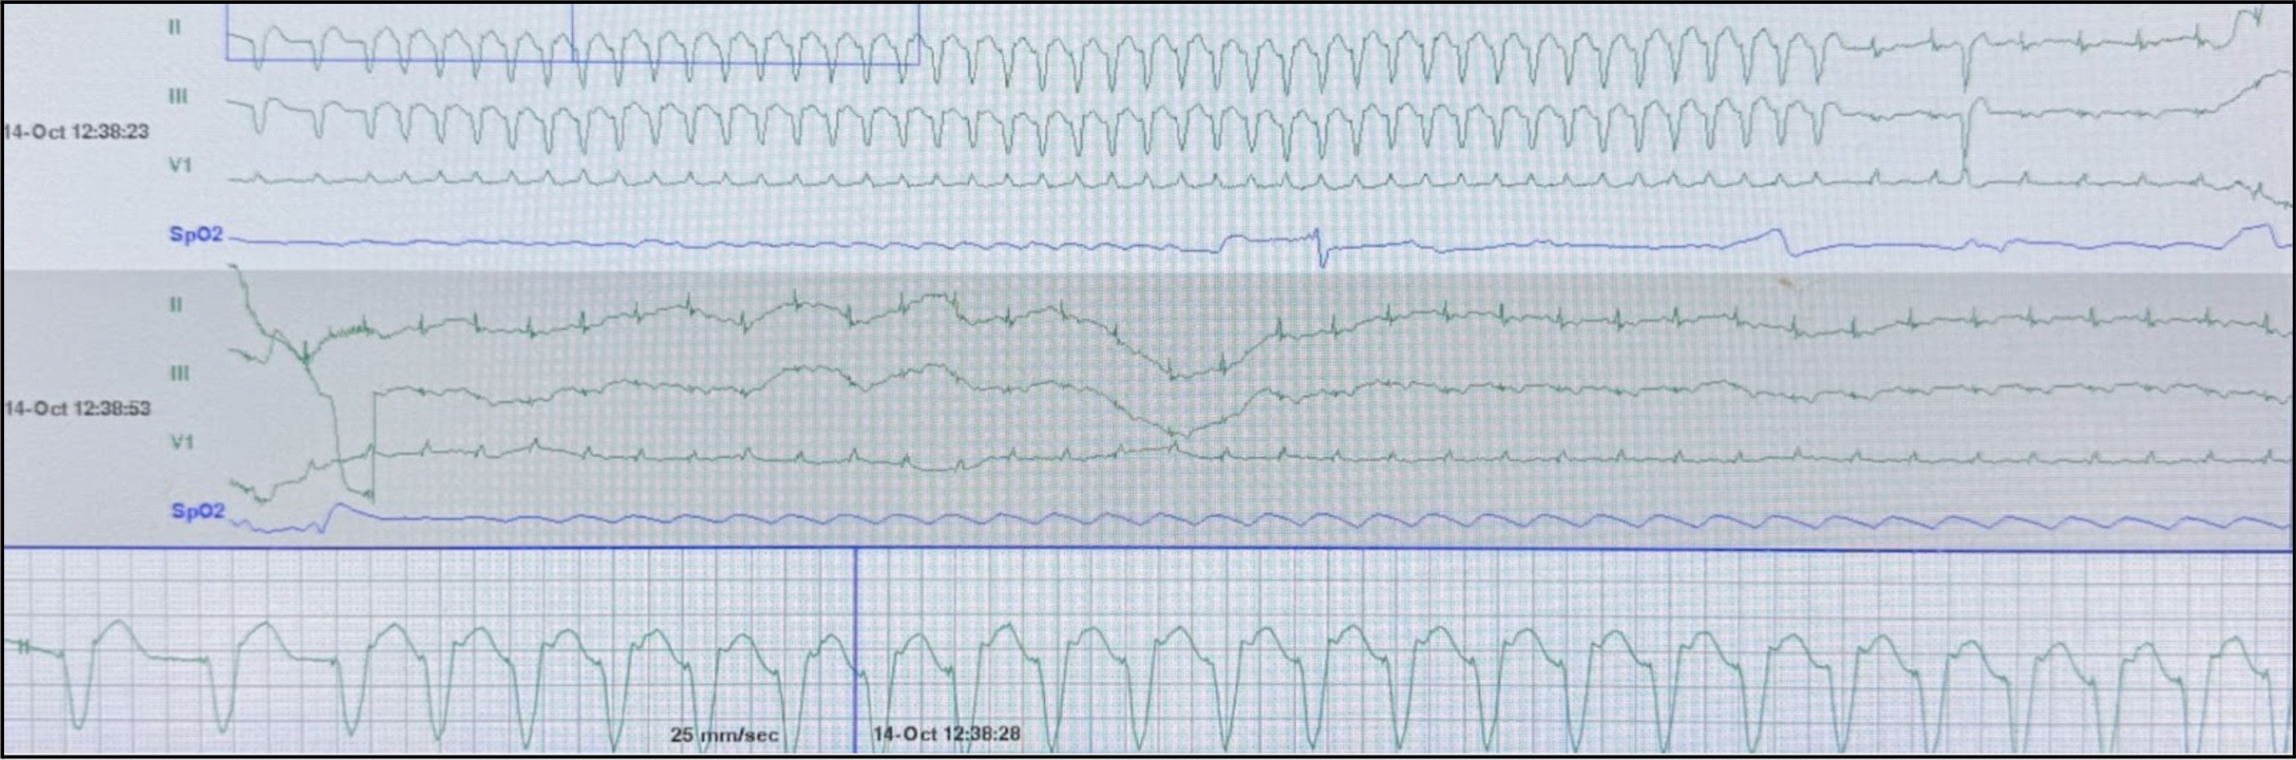

A 74 year old male with history of STEMI s/p PCI with DES of LAD and RI, HFrEF (EF 20-25%), sick sinus syndrome s/p DC-PPM, atrial flutter, hypertension, insulin-dependent diabetes, severe PAD s/p right IR SFA stent, and pancreatic insufficiency presenting for hypotension from general surgery clinic. The patient is brought to the resuscitation bay and while you are waiting for your work-up the monitor alarms and shows the following (Figure 1).

So, how was the diagnosis made? When looking closely at Figure 1, we notice what appears to be retrograde p-waves appearing just after the wide QRS complex (Figure 3).

When considering the native rhythm seen in Figure 2, paced sinus rhythm with RBBB, and the arrhythmia of wide complex tachycardia with retrograde p-waves seen in Figure 1, this highly supports the diagnosis of pacemaker mediated tachycardia (PMT). PMT is a re-entrant tachycardia where the pacemaker forms the anterograde pathway and the native pathway through the AV node forms the retrograde pathway, creating an endless-loop, similar to antidromic AVRT [1]. This antidromic loop results in the observed retrograde p-wave after ventricular depolarization as the atria are depolarized after the ventricles via the native retrograde pathway.